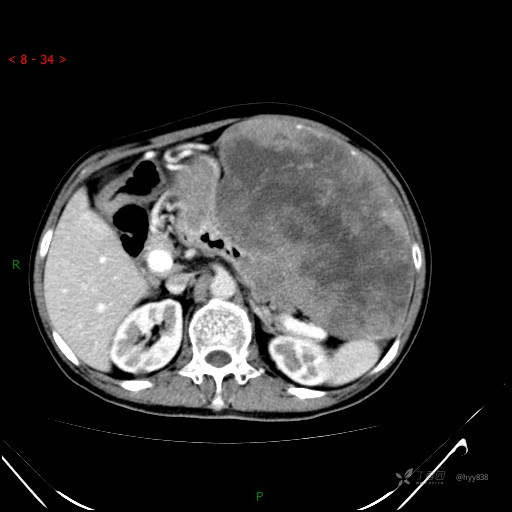

增强静脉期